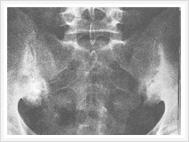

以骶髂关节炎最为突出。骶髂关节出现x线征象时往往已较迟,几乎完全是双侧性。最初出现的是关节附近

退变性骶髂关节炎

有斑片状骨质疏松区,特别是骶髂关节的中下段最为明显。接着便出现了骨腐蚀与软骨下骨皮质硬化。在骶髂关节的中下段,髂骨面覆盖着薄层软骨,因此该处首先出现骨骼变化,且比较明显。在骶髂关节的上1/3处,有坚强的韧带连接着骨面,也可以有类似的X线征象。

软骨下骨侵蚀的X线表现为关节间隙的假性增宽。接下去便是纤维化、钙化、骨桥形成与骨化。一般说来,软骨下骨皮质硬化比骨腐蚀明显些,最终骶髂关节完全强直,通常需数年之久。